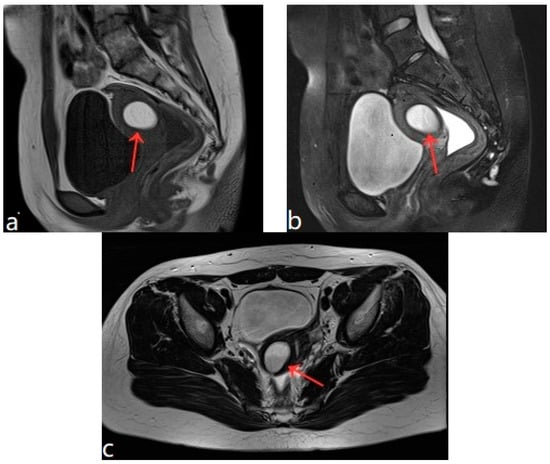

Figure 4.

Pelvic MRI shows lesions after HIFU treatment (5th year) (red arrows).